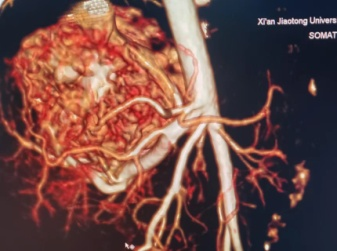

患儿妈妈怀孕期间产检发现肝脏占位,血运丰富,并随着时间的推移,肝脏占位逐渐变大,孕38+5周外院彩超提示肝脏肿块增长至7.3*4.3cm。宝宝出生后第一天即出现拒乳、呼吸困难、心率快等表现,考虑宝宝的情况为肝脏的血管瘤并有肝动-静脉瘘,引起心脏持续高动力状态,导致心功能不全,这是一种能够危急患儿生命的紧急情况,需要及早干预治疗,家属遂即慕名转至我院新生儿科。入住新生儿科后王惠萍教授紧急联系B超室乞艳华副教授完善心脏以及肝脏彩超评估患儿心功能以及瘤体大小,宝宝的肝脏占位正逐渐增大,心功能逐渐恶化,留给家属和医生的时间正在减少;小儿外科高亚教授心系患儿安危,多次查看、询问患儿情况,并根据每次复查指标,作出指示:决定使用微创介入的方式进行肝动脉栓塞术,封堵肿瘤血供。但新生儿血管纤细,动静脉瘘广泛,新生儿设备、管路、用药禁忌等诸多难题,成功的案例国内外鲜有报道,西北地区尚无类似病例报道。为了给患儿争取生存的机会,组织影像科介入组、小儿外科、麻醉手术科、医用超声科、新生儿科等院内多学科MDT团队进行了评估以及手术方案讨论, 反复论证手术的可行性,提出手术可能存在的风险以及应急策略并做好充分准备。

3月13日,在小儿外科高亚教授、郑百俊教授及郭新奎教授及多学科的积极配合下,为患儿进行了肝动脉造影术+肝动脉栓塞术。新生儿股动脉纤细,常规股动脉鞘作为入路存在术后股动脉闭塞下肢缺血风险,采用了经股动脉单纯微导管超选择性栓塞,手术难度大大增加,但避免了股动脉缺血风险。

在麻醉科(吴刚副主任,罗倩倩、陈趟医生)和新生儿科(王惠萍教授、王莉医生)的保驾护航下、超声科(何鑫医生)的精准定位置管,血管介入团队(彭玉萍教授、刘强教授、杨晓东医生)经过3小时的努力,共封堵四处肝血管瘤的主要供血动脉分支,手术过程患儿生命体征稳定,血管瘤的血流量逐渐减少,进行心功能测定显示心输出量较术前下降,效果显著,肝脏的“扫雷”行动获得阶段性的成功,在场的所有医务人员为孩子鼓掌加油!